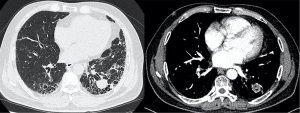

Chest CT images were reviewed by two pulmonologists and one radiologist in a blinded manner. Diagnosis of ILD was based on the presence of hallmark manifestations on chest CT (13,14), including honeycombing, traction bronchiectasis/bronchiolectasis, reticulation, ground-glass opacification, and consolidations. Reticulation, ground-glass opacification and consolidations are typically diffusely or patchily distributed in both lungs, with a subpleural or peribronchovascular predominance. The diagnostic criteria for IPF were in accordance with the updated IPF guidelines (15). The high-resolution CT (HRCT) patterns were classified as the UIP pattern or the probable UIP pattern accordingly (15). Typical CT images are presented in Figure 2. Acute exacerbation (AE) of IPF was defined according to the criteria proposed by the 2016 International Working Group Report (16).